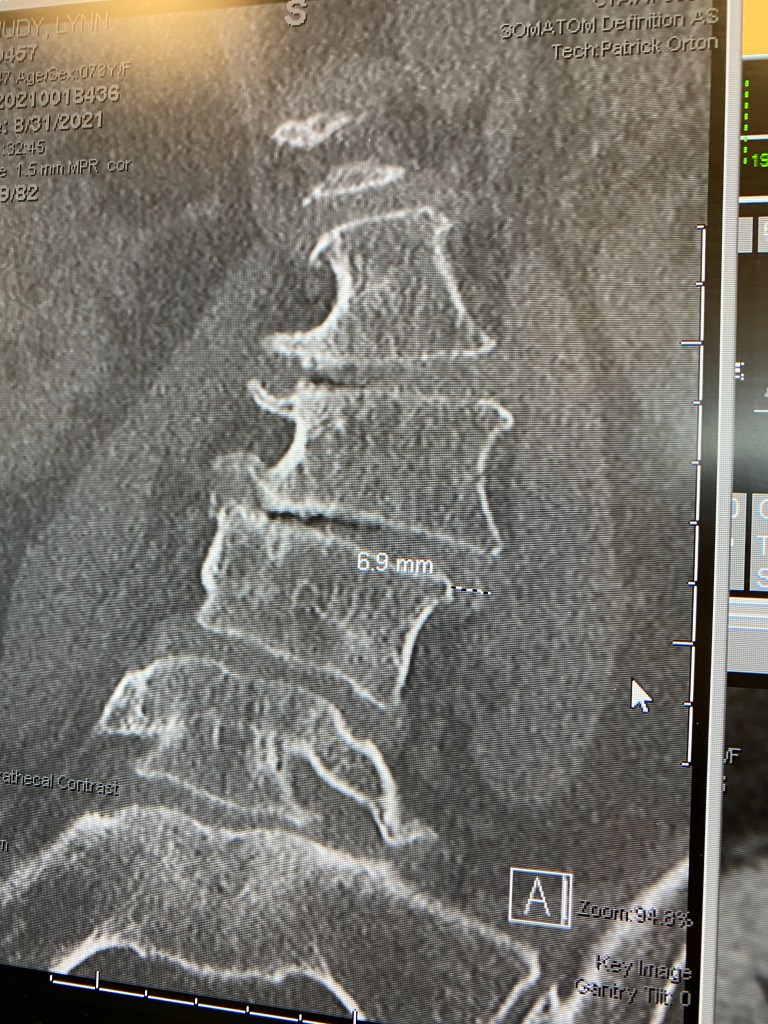

Once more into the fire, and tomorrow the answers start showing up… did we find the right nerve? Will fusion be the fix? Will I get my life back? Those are the operative questions, see what I did there?

None of this would be happening without Kim, who told me from the beginning that he was going to keep looking for whatever would stop the pain. I was 57 when he married me, skeletal from grief anorexia and fried from years of caregiving and loss, but still a house afire and totally into living life. Fast-forward to 2021 and increased degeneration from the accident I told you about… https://playingfortimeblog.com/2021/10/04/a-fractured-fairytale/ … has nearly immobilized me, so it’s gradually become a fact of life to be dealt with… will I stay on my own two feet, or is that becoming history?

This fall, with things clearly falling apart in the pillar that holds me upright, Kim raised the ante and went in search of any helpful information available. A PickleBall friend told him about his wife, my age, who had robotic-assisted spinal surgery in Kansas City and is walking again without pain. Another PickleBall buddy told us about her own friend, my age, who had yet another KC surgeon do the same surgery, with similar positive results.

Boys and girls, medical robotics have arrived in the heartland and the Young Turks are on it. A primary factor in our move to Lawrence was the stellar medical community here and in next-door Kansas City, and that’s been proven wise over and over. We’ve had critical need for their gifts many times in the eight years we’ve lived in this Kansas cocoon, and nobody has disappointed us so far. And before we’d even settled in, Kim started making himself part of the neighborhood, the community… local… bringing us now to a personable young surgeon with a shiny resumé who knows how to “fix it.”

So tomorrow we’re going to fix it. Please keep a good thought.

Not this part…

not even the trainwreck in the middle, just one key spot.

The x-rays are this side of obscene, but the amazing fact is that I stand straight… I just can’t keep moving for more than a few minutes.